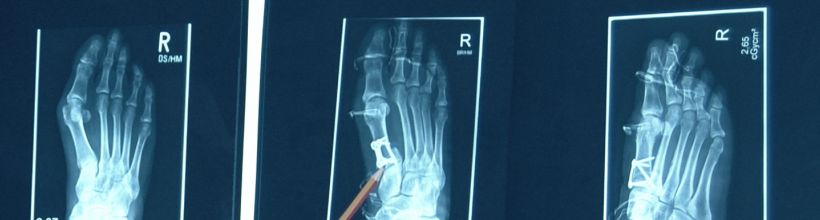

Hallux valgus (schmerzhafter Großzehenballen)

Ein schmerzhafter Großzehenballen ist die häufigste Zehenfehlstellung. Hierbei kommt es zu einer Abweichung der großen Zehe und einer sichtbaren knöchernen Vorwölbung. Die Haut über diesem Bereich erscheint gerötet und entzündlich. Im Rahmen der Operation wird diese Abweichung normalisiert, erster und zweiter Mittelfußknochen werden parallel eingestellt.